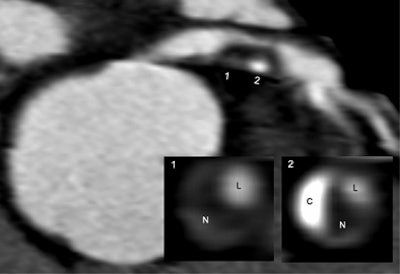

| Plaque type 3 (mixed, predominantly noncalcifying) was identified in a 68-year-old man with de novo unstable angina pectoris. Interventional coronary angiography confirmed proximal 90% stenosis of the left anterior descending (LAD) artery. Inlay bottom-right: Images 1 and 2 show cross-sectional images of the plaque. N = noncalcifying plaque component, C = calcifying plaque component, L = lumen. |